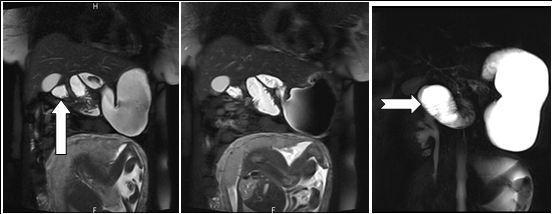

A 28 weeks and 4 days pregnant, 29 years-old female, known for an L4-L5 discopathy and a past history of surgery for appendicitis at the age of 10 (right-positioned appendix, not perforated), consulted with vomiting and abdominal pain in the epigastric region. Eating and drinking had become impossible at that point. Blood tests revealed pathologically elevated white blood cells count (11.4 G/l for a normal value of 4-10 G/l) and elevated hepatic tests. Preeclampsia and HELLP syndrome were ruled out, as were frequent causes for hepatitis (virus, medicines, auto-immunity). Abdominal echography did not reveal any sign of cholecystitis or pancreatitis and testing for urinary cause was negative. The second blood tests revealed a worsening of the hepatic tests, reason why the patient underwent a cholangio-MRI. This test did not reveal any biliary lesion but volvulus was suspected due to apparent intestinal malrotation. Obtruction was confirmed by gastroscopy (without scope) and situated at the level of the jejunum. Final confirmation of obstruction and its position in the abdomen was also obtained through intestinal MRI (see Figure 2A, Figure 2B, Figure 3). During this time, the patient never displayed any gynaecological signs and foetal echography revealed a foetus with cephalic position, weighting 1300g and a posteriorly inserted healthy placenta with a Manning score of 10/10. The patient was referred for surgery. She underwent an exploratory laparoscopy that revealed multiple adhesions of the small intestine. Volvulus of the small intestine was identified just at the level of the duodeno-jejunal angle, situated on the right side of the aorta. Removal of the adhesions was attempted but ended up causing a small lesion of the small intestine, prompting the transformation of the laparoscopy into an open laparotomy. The laparotomy revealed a volvulus of the small intestine with common mesentery, with encircling of the caecum, the last part of the ileum and the beginning of the jejunum by the omentum. Resolution of the volvulus showed absence of intestinal rotation at the duodeno-jejunal angle, confirming the presence of malrotation. Mesentery was repositioned (without Ladd’s procedure) and fixation of the right colon to the right peritoneum was performed. The small intestine, which showed no sign of ischemia, was sutured and adhesions were completely removed. A few hours after the surgery, the patient presented with uterine contractions every two minutes and uterine ultrasonography showed a 33mm cervix. Tocolysis was immediately given with good results and the contractions definitely ceased and did not reappear two days later when treatment was stopped. During her stay, the patient presented with left basal pneumonia that was treated with antibiotherapy. She completely recovered during the following days and was then discharged with no further complication. The rest of her pregnancy went without any other complication and the patient delivered with instrumentation (Kiwi-sucker) at the age of 40 weeks and 0 days due to a suspect cardio-tocogramm and absence of delivery progression. Both baby and mother were healthy and they were then discharged with no further complication

Figure 2A.Axial contrast-enhanced MRI scans show characteristic whirpool appearance of bowel and mesentery wrapping around superior mesenteric artery

Figure 2B.Axial contrast-enhanced MRI scans show characteristic whirpool appearance of bowel and mesentery wrapping around superior mesenteric artery

Figure 3.Coronal reformatted image shows contrast agent–filled small bowel on right

In that aspect, small bowel volvulus should always remain in the differential diagnosis in front of a pregnant woman presenting with abdominal pain during pregnancy, especially one like ours that was known for a previous surgery for appendicitis (a possible reason for the presence of the adhesions). Radiologic diagnosis of small bowel volvulus can be done by several technics. Plain abdominal film can be used, showing sometimes a typical pattern of dilated loops, but more often showing a normal radiological pattern due to a proximal position of the volvulus (with the loops being filled with liquid). Evidences on CT-scan are the presence of dilated bowel loops, intramural gas and the “whirlpool sign” (Cong et al, 2014; Shui et al, 2011)4, 12, but the use of technics exposing the foetus to radiations is debated. However, in their review, Cong et al 4emphasized the fact that those technics (and particularly plain radiography) are considered safe for the mother as well as for the foetus (Cong et al, 2014)4. MRI is also safe and extremely precise in the diagnosis of small bowel obstruction (Vassiliou et al, 2012)13, sometimes also showing the “whirlpool sign” (Kouki et al, 2013)7 and ultrasonography has been reported to be useful in some instances (Cong et al, 2014)4 but it can also remain completely negative. In our case, while cholangio-MRI suggested the diagnosis, final diagnosis was given by intestinal MRI, showing a possible role for this technic in some unusual cases, in which doubts about the diagnosis or about the state of different abdominal structures remain. However, in cases in which clinical symptoms, laboratory and more basic radiological (plain abdominal film of CT-scan) are highly suggestive of this pathology, exploratory surgery should be started at the earliest time possible.